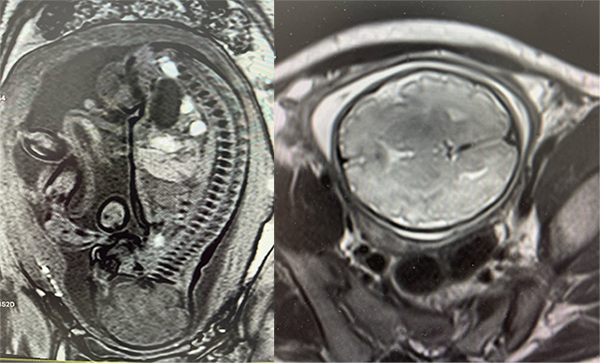

2024年10月17日,首都医科大学附属北京儿童医院成功完成了首例胎儿磁共振检查,意味着我院医学影像检查迈出了新的一步,也是对出生结构缺陷患儿从胎儿开始提供全生命周期连续性医疗服务进行影像诊疗的开端,该检查为安全、精准的早期胎儿评估、早期干预提供了强有力的技术支撑。

该患儿在外院曾进行过三次胎儿磁共振检查,均未成功。在北京儿童医院检查当天,影像中心技师骨干通过精准的操作及影像图像处理,生成了高质量的胎儿影像资料,孕妇在医技人员的细心指导下,顺利完成了磁共振扫描。整个检查过程中,设备运行平稳,清晰地显示了胎儿相关检查部位的解剖结构,图像采集迅速高效,为后续的临床决策提供了重要依据。

胎儿磁共振检查(Fetal MRI)作为一项非侵入性诊断技术,其独特优势在于无电离辐射的情况下,可清晰呈现胎儿体内结构,尤其是对胎儿中枢神经系统、肺部、心脏等复杂器官的发育情况提供高分辨率图像。北京儿童医院影像中心采用的先进磁共振检查设备,提供了高质量的图像与更低的噪声干扰,可为临床医生提供了更为详尽、准确的信息。